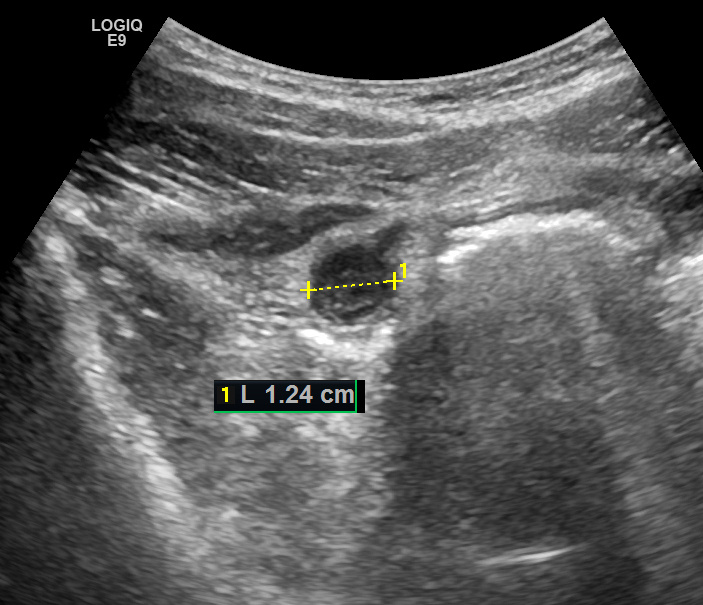

Это наблюдение - просто из разряда "красивых", когда патология наглядна, легко определяется, и вся симптоматика не вызывает сомнений. Пациент 30 лет поступил в отделение ультразвуковой диагностики по направлению дежурного хирурга с жалобами на интенсивные боли в правой половине живота. Клиническая картина развивалась "классически" - начало с болей в эпигастрии с последующим смещением вправо. В срочном анализе крови - лейкоцитоз. При ультразвуковом исследовании аппендикс располагался кпереди от купола слепой кишки, и поэтому сразу был визуализирован, даже конвексным датчиком. Подобное расположение аппендикса встречается нечасто - обычно он располагается медиальнее купола и почти всегда частично прикрыт петлями кишечника, что позволяет его визуализировать только фрагментарно. При поверхностном расположении аппендикса удается его визуализировать на всём протяжении - от устья до кончика. Видео 03. Визуализация аппендикса на всём протяжении. Обратите внимание, что удаётся визуализировать д

ОСТРЫЙ АППЕНДИЦИТ. ВИЗУАЛИЗАЦИЯ НА ВСЁМ ПРОТЯЖЕНИИ.